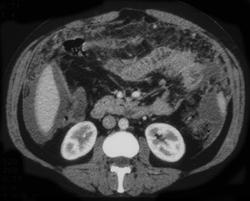

女,68y,下腹疼3月,一月半前院外ct示上腹未见异常。近1月来,症状加重。4天前入院,b超示胸腹水。今日呕吐频繁。  生化检查:  结核抗体阴性,血沉18mm/h, 癌胚抗原阴性,胸水细胞学检查见多数淋巴细胞。 白细胞总数5.4x10^12/l,血红蛋白104g/l.

腹部检查怎么不服造影剂?片内仅能诊断为腹腔积液,是什么原因还需要进一步查。

患者右中腹部肠管聚集,内密度不均,可见片絮状及结节样增密影,小肠壁增厚,与之相邻处有软组织影。

腹腔积液可以肯定,原因?右侧下腹肠壁增厚,周围脂肪密度增高,粘连坏死?---梗阻坏死(不像)还是血栓坏死,占位?期待结果。

肠系膜可见梳征,不除外克罗恩氏病.腹水,建议气钡双重造影,灌肠.

绞窄性肠梗阻,合并腹膜炎、腹水、肠粘连。

1)右侧腹腔前部见类似“网膜饼”样改变,考虑网膜转移瘤。2)腹水。

腹膜污染[大网膜增厚可见污垢征及小班结与饼片影,肠系膜增厚],大量腹水。考虑癌性腹膜炎,建议查腹水。结核待排.注意上腹部及胃肠道检查